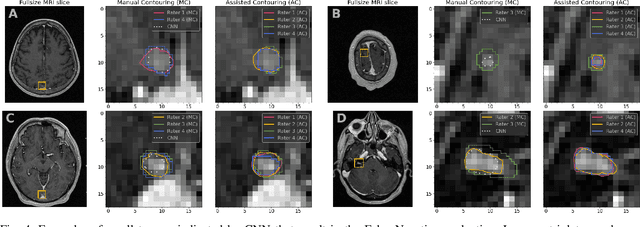

Abstract:Stereotactic radiosurgery is a minimally-invasive treatment option for a large number of patients with intracranial tumors. As part of the therapy treatment, accurate delineation of brain tumors is of great importance. However, slice-by-slice manual segmentation on T1c MRI could be time-consuming (especially for multiple metastases) and subjective (especially for meningiomas). In our work, we compared several deep convolutional networks architectures and training procedures and evaluated the best model in a radiation therapy department for three types of brain tumors: meningiomas, schwannomas and multiple brain metastases. The developed semiautomatic segmentation system accelerates the contouring process by 2.2 times on average and increases inter-rater agreement from 92% to 96.5%.